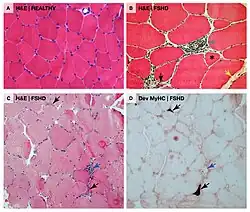

Muscle histology

Unlike other muscular dystrophies, early muscle biopsies show only mild degrees of fibrosis, muscle fiber hypertrophy, and displacement of nuclei from myofiber peripheries (central nucleation).[27] More often found is inflammation.[27] There can be endomysial inflammation, primarily composed of CD8+ T-cells, although these cells do not seem to cause muscle fiber death directly.[27] Endomysial blood vessels can be surrounded by inflammation, which is relatively unique to FSHD, and this inflammation contains CD4+ T-cells.[27] Inflammation is succeeded by deposition of fat (fatty infiltration), then fibrosis.[81][27] Individual muscle fibers can appear whorled, moth-eaten, and, especially, lobulated.[82]